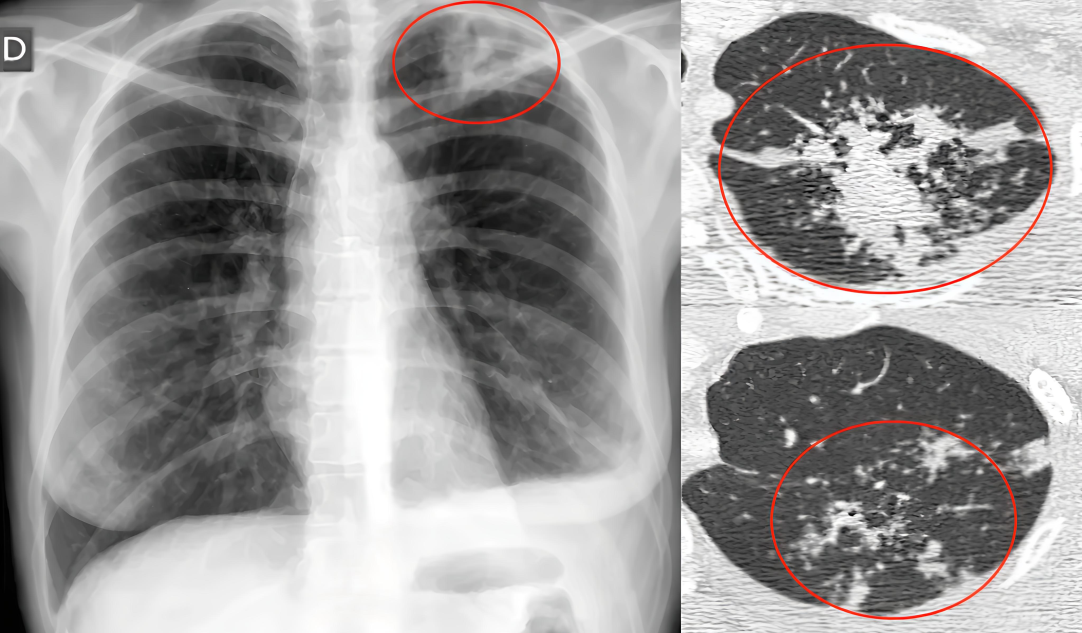

肺结核至今仍然是危害我国人民身体健康的重大传染病之一,虽然随着我国现代医疗卫生事业技术水平的不断提高,在结核疾病诊断、药物治疗上已经取得了很大的进步,在临床治疗诊断过程中,为了不断提高我国肺结核相关疾病的临床发现准确率和临床治愈率,影像诊断技术的指导作用更加不可或缺,常规X线胸片是目前肺结核早期检查的首选,但螺旋CT在肺结核疾病诊断中发挥越来越重要的指导作用。

胸部X线片在肺结核诊断中是最传统,简捷而快速的一种检查方式,对病变部位,范围和性质并诊断有重要价值,但是平片成像的组织重叠,对病变的详细结构观察较差,而且早期肺结核病灶较小,很难发现病灶并作出诊断,因此具有局限性,适用于肺结核的初步筛查。而螺旋CT克服了平片的局限性,无多组织重叠,还可以通过后期重建技术显示病灶更多的细节,因此螺旋CT在肺结核的诊断中的应用价值更加广泛。